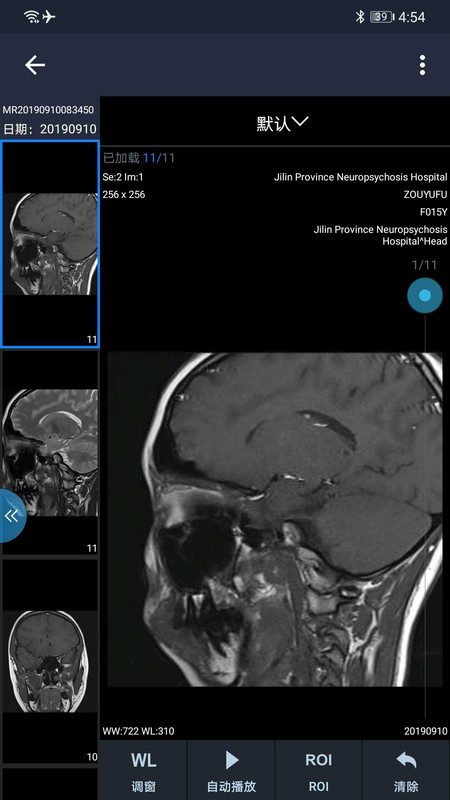

1、打开和缓医疗APP,进入影像查看页,点击左侧影像缩略图,可切换显示不同部位影像,配合下方功能键,辅助分析诊断。